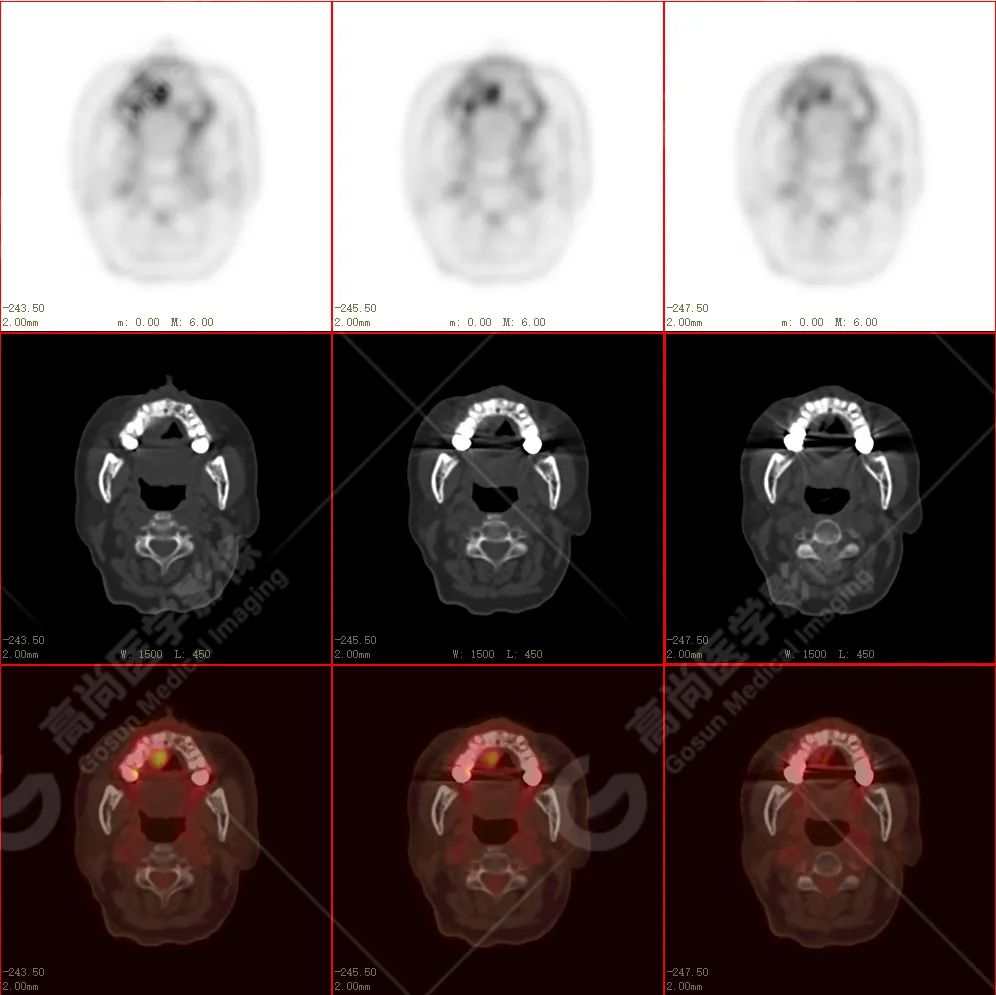

右侧上颌骨-上颌窦骨壁-骨性鼻中隔区域见片块状放射性摄取异常增高影,最大层面约 4.1 cm×3.8 cm×2.8 cm,SUV 最大值为 10.4,CT 示上述部位见成骨性改变,骨质不均匀弥漫性增厚、密度不均匀增高,并可见肿瘤骨影,边缘毛糙,周围伴软组织增厚。